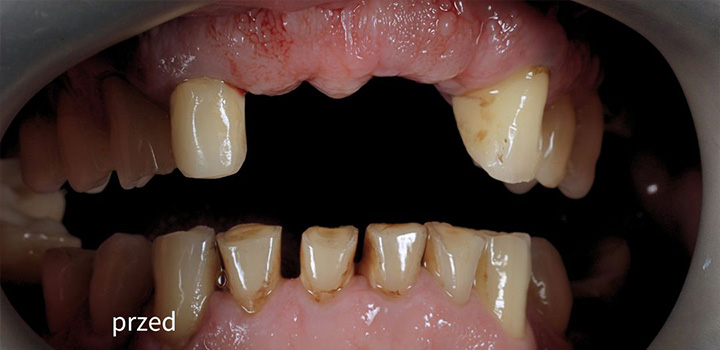

Efekty, które mówią same za siebie